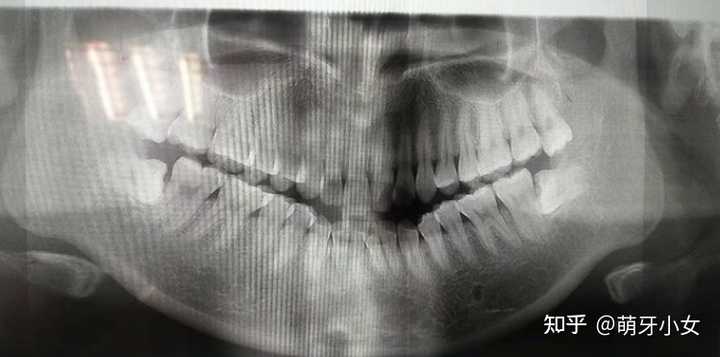

Apr 17, 21 · 这种智齿是必须要拔掉才可以的 当然也有例外 比如说万一智齿长得还行 然后哪颗牙齿又有了点问题 那就可以把智齿留下来 把问题牙拔了 然后再通过矫正 把牙齿拉到正常位置 这时候智齿就可以发挥它原本的备胎作用了 一般来说 如果智齿反反复复在发炎 某智齿对侧没有对象Mar 16, 19 · 智齿是可以不拔的,但是具体要看智齿的情况决定。智齿一般是18周岁以后开始长的,长智齿之后可以先到口腔科就诊,让医生拍张曲面断层片看口内所有智齿的情况,如果智齿长得比较正,也有足够的空间萌出,并且也有对颌的智齿,能够形成良好的牙齿咬合关系,那么可以考虑保留支持,不用拔。智齿不一定要拔。 一般情况下,如果长智齿没有什么不良症状的发生,如果智齿的生长位置正确, 可以选择不拔,但是如果智齿有长 蛀牙 ,或者疼痛明显、智齿和其他牙齿排列过紧等,一般在照X片后根据医生的建议可以选择拔智齿。